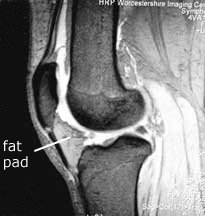

Note the relationship of the fat pad to the patellar tendon, and hence the extensor mechanism. It fills the space from the patellar tendon all of the way to the cruciate ligaments. In fact, it also extends sideways, making the bulge that one can often see in a normal knee on either side of the patella (red arrow). Normally the fat pad is not attached to either the meniscus or the patella, and is separated from the patellar tendon by the deep infrapatellar bursa.

With arthrofibrosis fat pad the fat pad becomes thickened and fibrosed, and the deep infrapatellar bursa can be obliterated. The fat pad can become adherent to the anterior horn of the meniscus and to the patella, and via the obliteration of the deep infrapatellar bursa it becomes adherent to the patellar tendon also. This thickened fat pad may also become tethered to the intercondylar notch where the cruciate lies.

Note also from the MRI that the fat pad is truly in contact with the bony lower edge of the patella. If that fat pad is scarred and contracted, can you imagine how it can pull the patella downward?